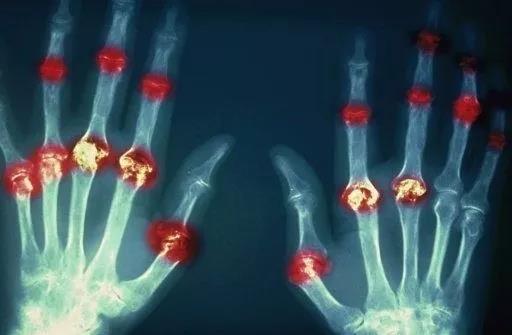

? 類風(fēng)濕關(guān)節(jié)炎

類風(fēng)濕關(guān)節(jié)炎是一種高度致殘的自身免疫性疾病,發(fā)病十年的患者中至少有50%的人失去勞動(dòng)能力。

類風(fēng)濕關(guān)節(jié)炎©Health Same of Flickr

1977年,Baldwin在用骨髓干細(xì)胞移植治療再生障礙性貧血的過程中,意外發(fā)現(xiàn)患者的類風(fēng)濕關(guān)節(jié)炎得到緩解。

2004年,歐洲骨髓移植和抗風(fēng)濕病聯(lián)盟對60例類風(fēng)濕病關(guān)節(jié)炎移植患者進(jìn)行回顧性分析,這些患者的關(guān)節(jié)破壞都達(dá)到不可修復(fù)程度,生活不能自理,通過干細(xì)胞移植治療后,67%的患者得到明顯緩解。

我國國內(nèi)多家醫(yī)院已開展了干細(xì)胞治療類風(fēng)濕性關(guān)節(jié)炎的臨床研究。首例自體干細(xì)胞移植治療類風(fēng)濕關(guān)節(jié)炎在北京協(xié)和醫(yī)院完成。經(jīng)過5個(gè)月隨訪,這些經(jīng)常規(guī)藥物治療失敗且病情發(fā)展迅速的患者,在接受干細(xì)胞移植治療后,癥狀均獲得改善,關(guān)節(jié)腫脹消失,各項(xiàng)檢查指標(biāo)恢復(fù)正常。

解放軍323醫(yī)院2011年的一項(xiàng)臨床研究中,27位患者(對照組)只使用藥物治療;另外153位患者(細(xì)胞治療組)在藥物治療的基礎(chǔ)上進(jìn)行臍帶間充質(zhì)干細(xì)胞輸注。結(jié)果顯示,治療組DAS28、HAQ 評分、ACR20較對照組下降明顯(分值越低,療效越好),Th1/Th2趨于平衡、Treg升高與臨床實(shí)驗(yàn)指標(biāo)及癥狀的緩解直接相關(guān)。